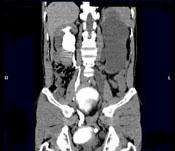

问题 男,55岁,尿频,尿痛伴低热乏力1个月。如图所示,下列说法正确的是 ( )

选项 A、左侧输尿管结核 B、左侧输尿管癌 C、右侧肾积水 D、膀胱变形 E、左侧输尿管多发性狭窄

答案 ACDE